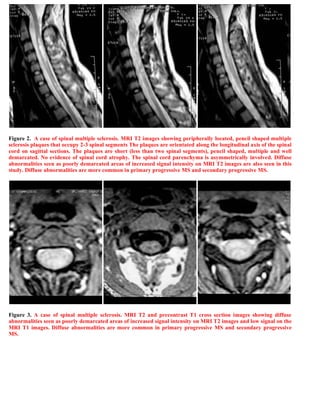

This document discusses a case of spinal multiple sclerosis in a 40-year-old patient. MRI images show well-defined pencil-shaped lesions occupying 2-3 spinal segments that are hypointense on T1-weighted images and hyperintense on T2-weighted images. Diffuse abnormalities are also seen as poorly demarcated hyperintense regions on T2-weighted images. The diagnosis is spinal multiple sclerosis. The document then discusses features of spinal MS lesions seen on MRI such as focal lesions, diffuse abnormalities, and spinal cord atrophy, and compares features of MS to other conditions like neuromyelitis optica.